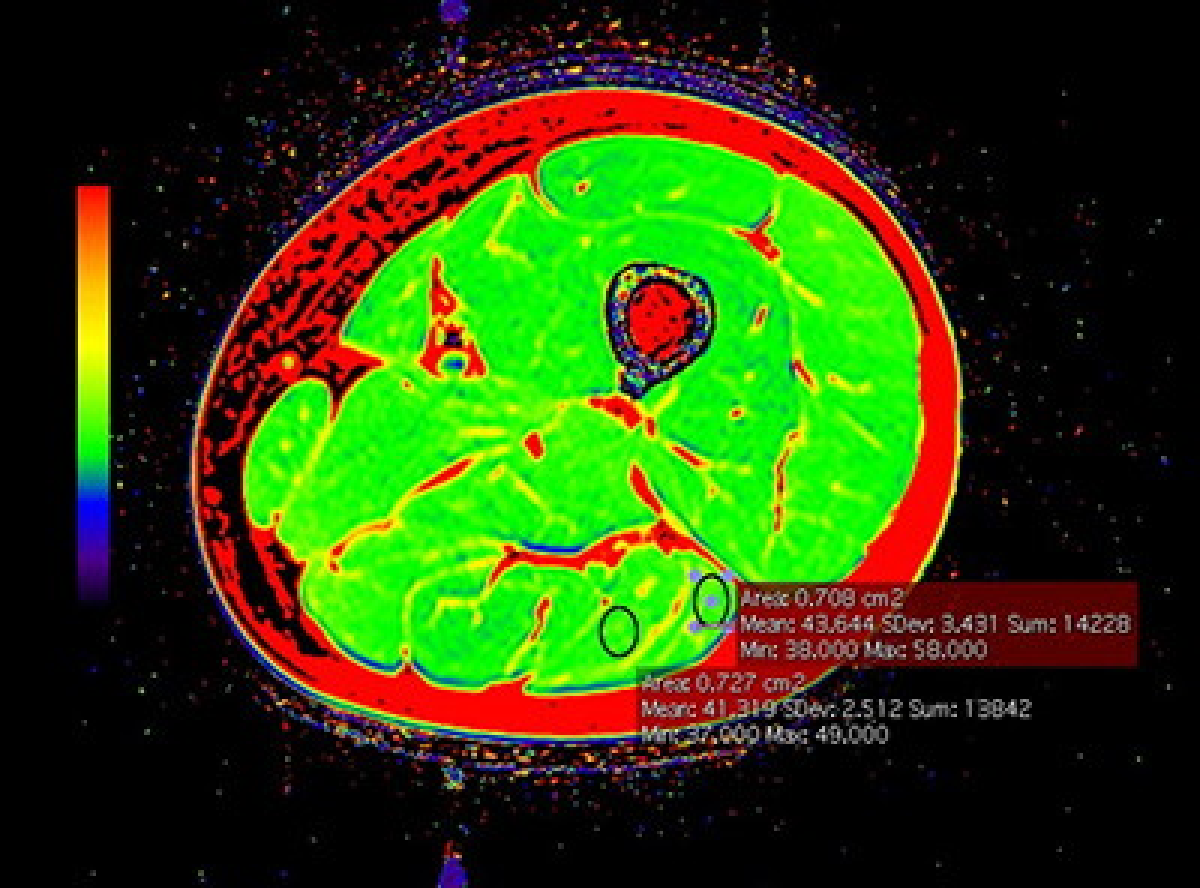

骨軟部

【T2map】

骨軟部腫瘍や脊椎疾患、スポーツ外傷、関節リウマチ、関節疾患など多種多様な疾患に対し、単純写真やCT、MRIを用いて画像診断を行っています。

また術前ナビゲーション画像作成など治療を補助する役割も担っています。